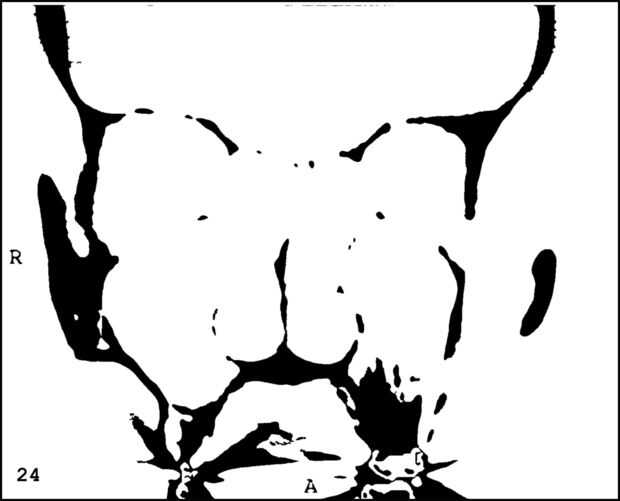

¡ Wow! Este fue por menos de 12 horas y tengo 1.000 visitas! Esto es sólo mi segundo instructable, así que estoy encantada. Decidí seguir adelante y publicar las imágenes que utiliza. Se trata de MRI de mi esposa, así que ella sólo puede tener lo mundos primer código abierto jefe. Mi lámpara utiliza solamente las primeras 16 capas, pero te di todos 34 que representa. Seguir adelante y usar estas imágenes, pero si lo haces, por favor me manden una imagen de lo que te ocurrió así que puedo hacerla sentir un poco famoso. ¡Que te diviertas!